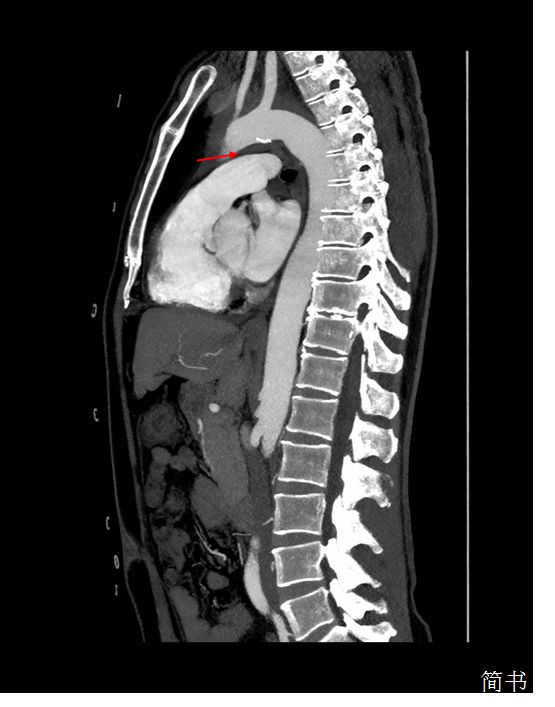

回过头来看我们这位患者,从主动脉CTA矢状位上可以发现主动脉弓与肺动脉间隙被壁内血肿填充(图*箭3**头处),解剖学上左侧喉返神经正好走形在此处,受到主动脉弓血肿压迫导致声带麻痹。至此,拨开疑云见阳光,患者的突发声嘶是因为——继发于主动脉壁内血肿的心室-声带综合征。

图3 主动脉CTA矢状位:箭头所指部位为主动脉弓与肺动脉间隙,可见该间隙被壁内血肿填充,左侧喉返神经从该间隙环绕主动脉弓后折返向上走形